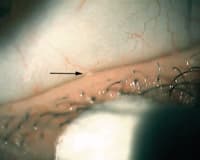

Figure 2. Meibomian

expression demonstrating a Grade 2 (thickened and opaque) secretion. |

Meibomian gland expression (Figure 2) 0 to 4 scale as in Table 1.

Meibography using clinical transilluminator (Figures 3 and 4) both lower lids, scale 0 to 4 as in Table 1.

Figure 4. Meibography demonstrating an area of normal glands (letter a) and gland dropout (letter b). |